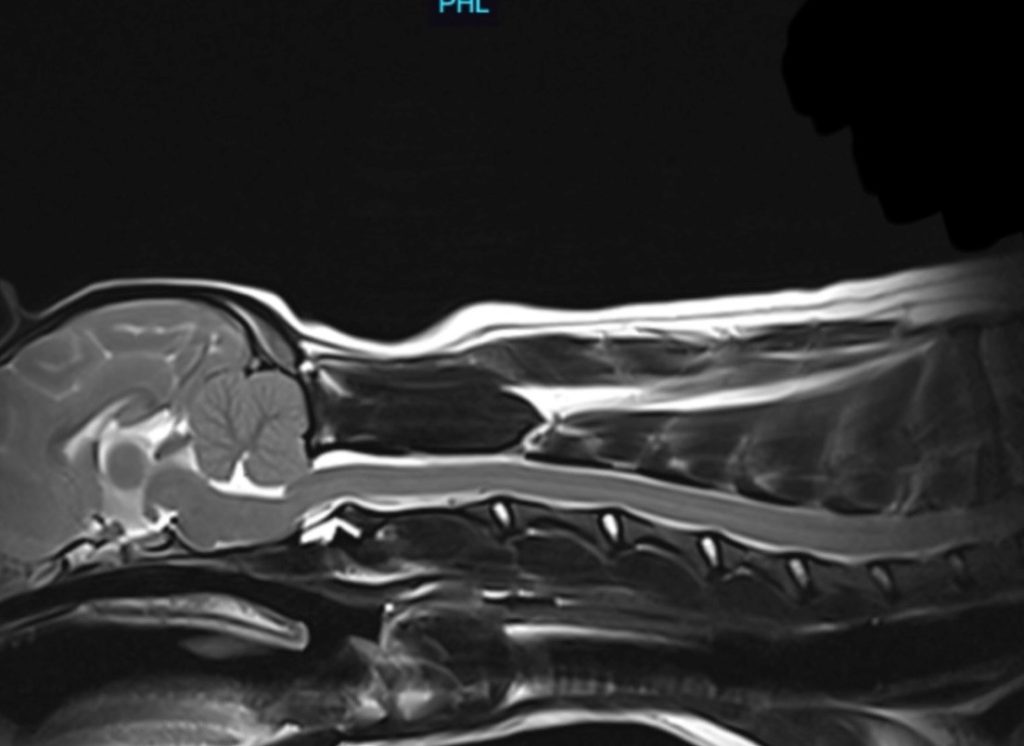

A “clear” scan: grading is CM2/SM0c. The dog has mild CM, no syrinx, no CCD, no dorsal banding, normal ventricles, and only mild medullary elevation.

A severely affected dog: grading is CM2/SM2a. The syrinx is 8mm. The dog also has significant dorsal banding, medullary elevation, and ventricular dilation.